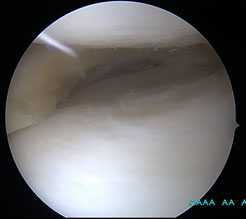

Продольные трещины на хряще большеберцовой кости после эпизода подкашивания после разрыва передней крестообразной связки коленного сустава.

Дегенеративные изменения суставного хряща коленного сустава появляющиеся на фоне повреждения разорванным мениском.